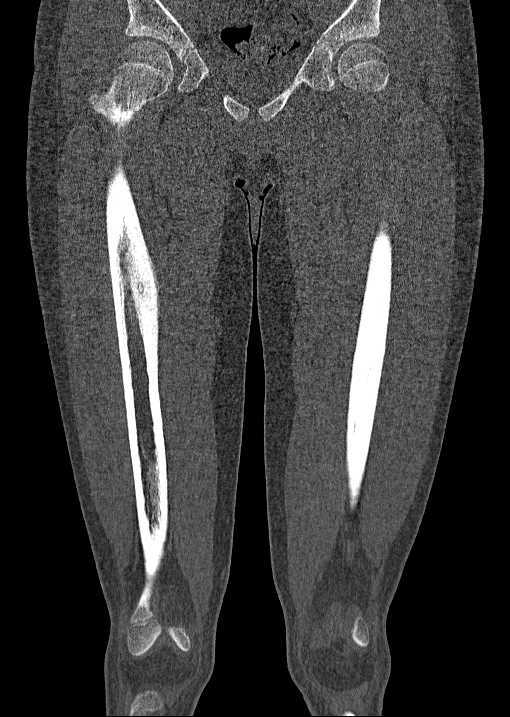

Worum handelt es sich bei der Knochenläsion am rechten Oberschenkel am ehesten? Anamnese: 12-jähriger mit nächtlichen Schmerzen des rechen Oberschenkels.